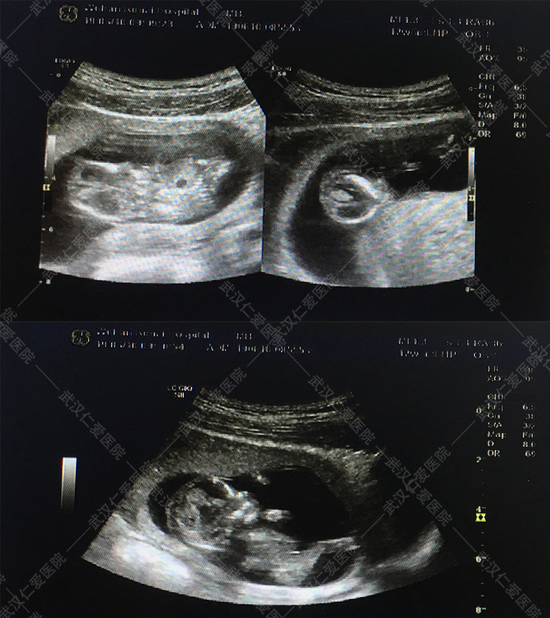

6月16號(hào),武漢仁愛(ài)醫(yī)院NT篩查出兩例畸形胎兒,一例多器官多系統(tǒng)畸形,一例露腦畸形,這兩位孕媽都是孕12周+,其中一位還是高齡產(chǎn)婦今年33歲,喜懷二胎,本來(lái)是高高興興的來(lái)做產(chǎn)檢,沒(méi)想到NT篩查出胎兒露腦畸形。

露腦畸形

對(duì)于NT檢查,很多孕媽不是很了解,認(rèn)為和普通B超差不多,甚至還有一些孕媽覺(jué)得NT篩查可做可不做。武漢仁愛(ài)醫(yī)院超聲影像科王娟主任解釋?zhuān)?ldquo;NT篩查主要是通過(guò)B超檢查胎兒頸部透明層較厚的部位,用于早期診斷胎兒是否存在唐氏綜合征等染色體疾病及其他發(fā)育異常,很多孕媽沒(méi)等做四維彩超就被確診畸形的,所以這項(xiàng)檢查不容忽視。”